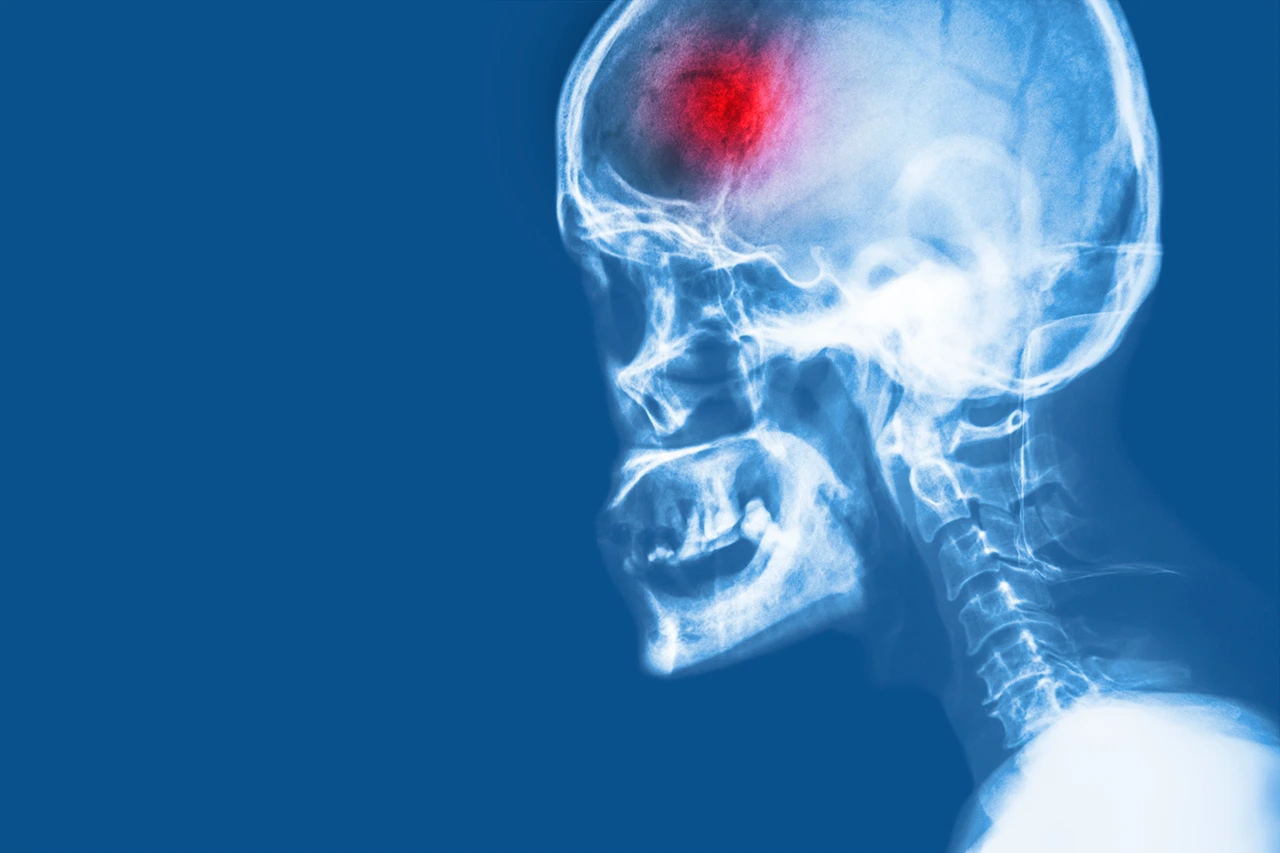

Cerebrovascular (isquémico)

Accidente cerebrovascular (isquémico):